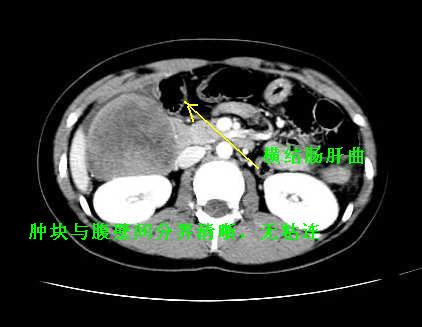

我坚决反对您的观点,该病例定位:横结肠肝曲与升结肠之间的肠系膜及部分肠壁。请看下图:

病灶巨大,少部分向肠腔内生长,大部分向长腔外生长。其密度不均匀,增强显示明显不均匀强化,并见有大片状始终不强化的不规则坏死液化区。虽然病灶中上部形态尚可,病人又如此年轻,但中下部形态、密度、强化特点强烈提示为恶性病灶。综上,我考虑本病例为:恶性胃肠道间质瘤。